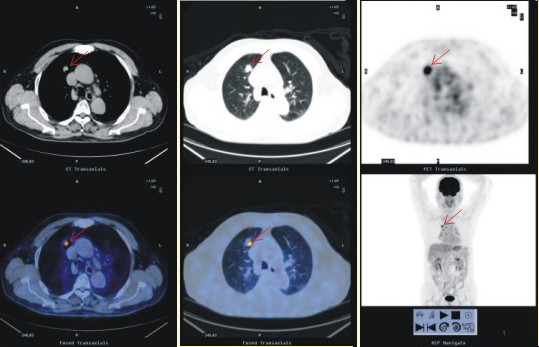

患者男性,76歲。5年前,PET-CT體檢發(fā)現(xiàn)右肺上葉微小高代謝灶,術(shù)后證實(shí)為早期肺癌。現(xiàn)患者全身情況正常,實(shí)現(xiàn)了腫瘤的早期診斷與根治。

2、 良、惡性鑒別及尋找原發(fā)灶和轉(zhuǎn)移灶

PET-CT顯像作為功能顯像,能夠揭示機(jī)體細(xì)胞代謝的異常變化,因而能較容易鑒別腫瘤是良性還是惡性;而PET-CT顯像能同時(shí)獲得PET與CT兩者的全身的斷層圖像,對于腫瘤原發(fā)灶與轉(zhuǎn)移灶的診斷尤為有利。